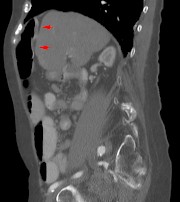

Das Chilaiditisyndrom oder Chilaiditi-Syndrom beschreibt in der Medizin eine Verlagerung und Drehung von Dick- und seltener Dünndarmanteilen von weiter fußwärts nach kopfwärts zwischen Zwerchfell und Leber.

Das Syndrom ist eher selten (unter 1 %) und wird meist als Zufallsbefund auf Röntgenaufnahmen der Lunge erkannt. Im Computertomogramm des Oberbauches fällt es ebenfalls auf. Auch im Ultraschall kann es erkannt werden, allerdings schwerer als im Röntgenbild. Bei Eingriffen an der Leber, insbesondere bei Leberpunktionen, ist die Kenntnis dieser anatomischen Variante von Wichtigkeit.

Es sind Anteile des Colons - vor allem der rechten Flexur - oder seltener des Dünndarms zwischen den rechten Leberlappen und das rechte Zwerchfell verlagert. Das Syndrom kann mit Fehlbildungen der Leber, des Zwerchfells oder Dickdarmes einhergehen.